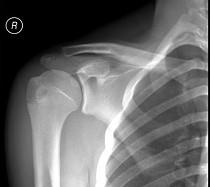

男,请根据其正常肩关节影像图像,判断其最可能的年龄 ( )A、36岁左右B、26岁左右C、46岁左右D、16岁左右E、56岁左右

问题 男,请根据其正常肩关节影像图像,判断其最可能的年龄 ( )

选项 A、36岁左右 B、26岁左右 C、46岁左右 D、16岁左右 E、56岁左右

答案 D